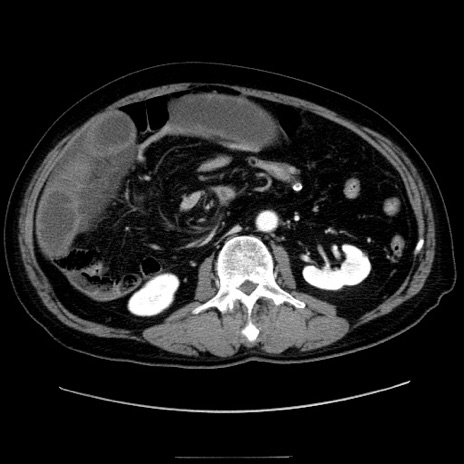

症例30(横断像)

【症例】80歳代男性

【主訴】臍周囲痛

【現病歴】約6時間前から臍下部痛が出現。次第に腹部膨隆・背部痛も生じてきたため来院。背部痛の場所は変化しない。

【身体所見】意識清明、BT 36.3℃、BP  131/87mmHg、P 87bpm、SpO2 100%(RA)、臍周囲自発痛・圧痛あり、反跳痛なし、自発痛部位に一致して板状硬あり、腹部膨隆、腸雑音減弱、CVA tenderness両側陰性。

【データ】WBC 19600、CRP 0.33